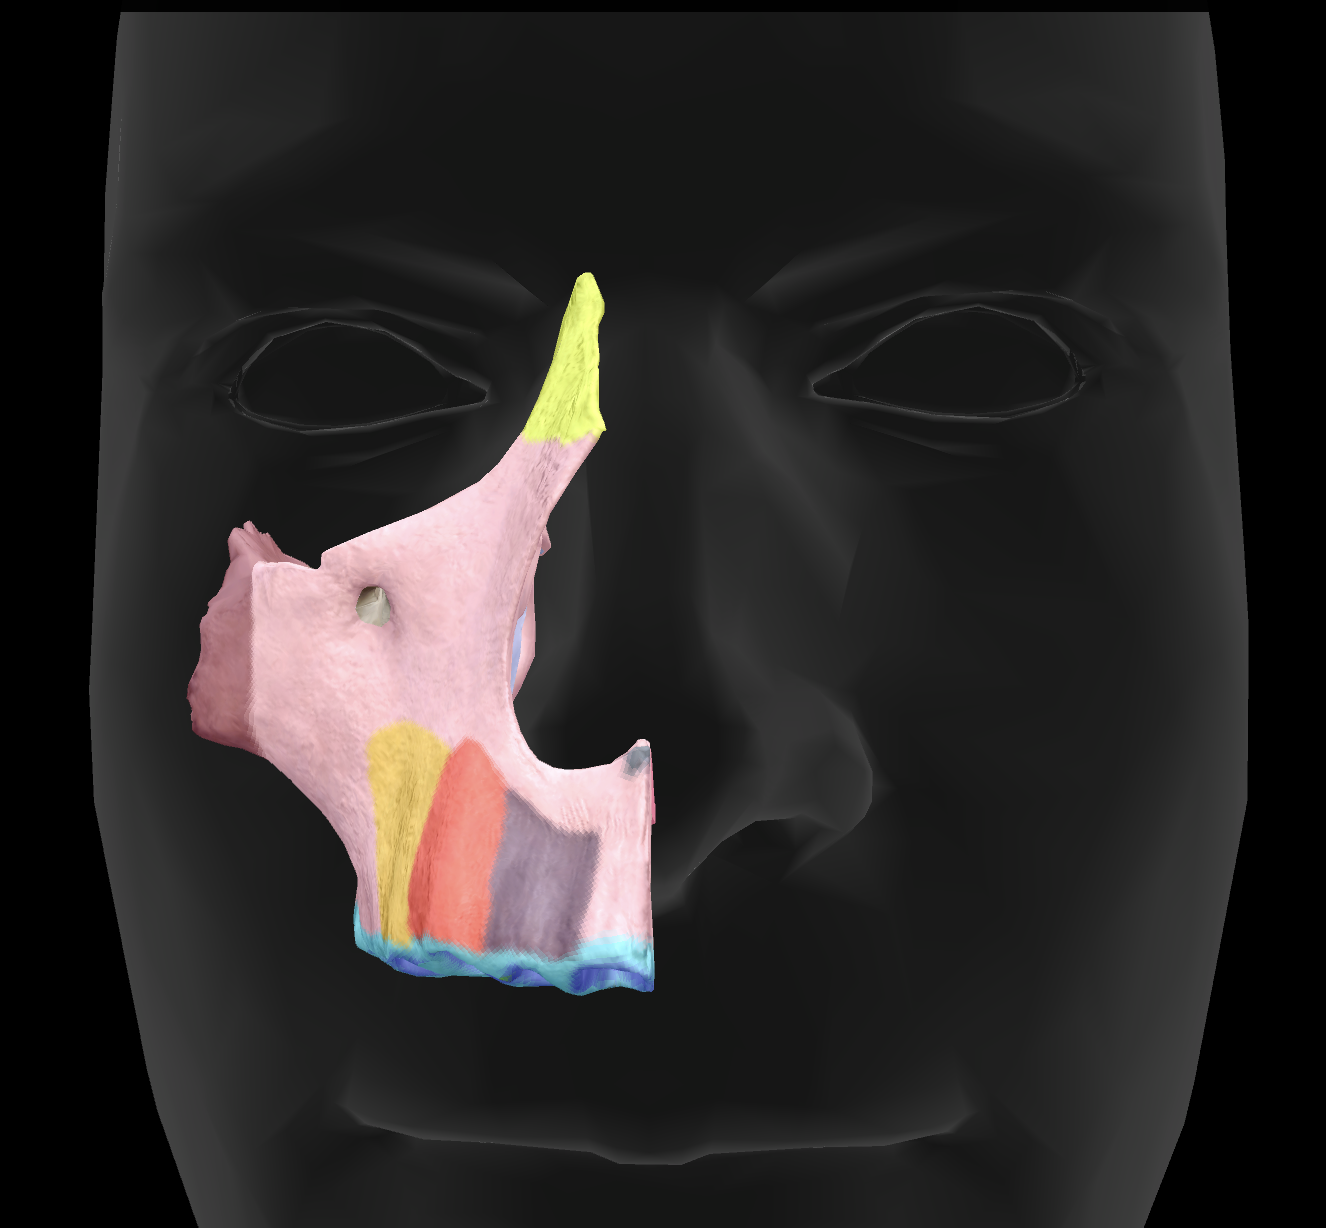

What is the name of this feature?

palatine process of maxilla

What is the name of this feature?

alveolar process

palatine process of maxilla

What is the name of this feature?

infraorbital foramen